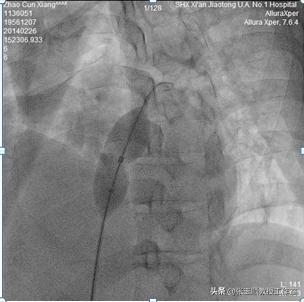

张玉顺教授团队,是全国技术力量最强、最有经验的PFO医疗团队,他们的优先考虑是,这个手术不复杂,关键是,术后能否改善患者症状。为此,他们先用球囊实验封堵,观察血氧变化,看是否有效。果然,如术前预计的那样,在球囊实验封堵前,王先生平卧位,股动脉氧分压63.6mmHg,氧饱和度92.8%;半卧位,股动脉氧分压48.2mmHg,氧饱和度85.7%;球囊实验封堵后,王先生平卧和半卧位氧分压无变化,均为股动脉氧分压72.0mmHg,氧饱和度95.8%。证明有效后,医生迅速更换了永久封堵器,结束了手术。

图5球囊试验封堵

术后王先生胸闷气短症状即刻得到改善,未吸氧状态下测经皮氧饱和度为97%,平卧位与直立位一致,氧分压由46mmHg上升至76mmHg。术后随访1月复查血气分析:平卧位,桡动脉氧分压79.3mmHg,氧饱和度95.4%;立位,桡动脉氧分压83.6mmHg,氧饱和度96.5%;平卧位与直立位基本一致,日常生活不受影响。